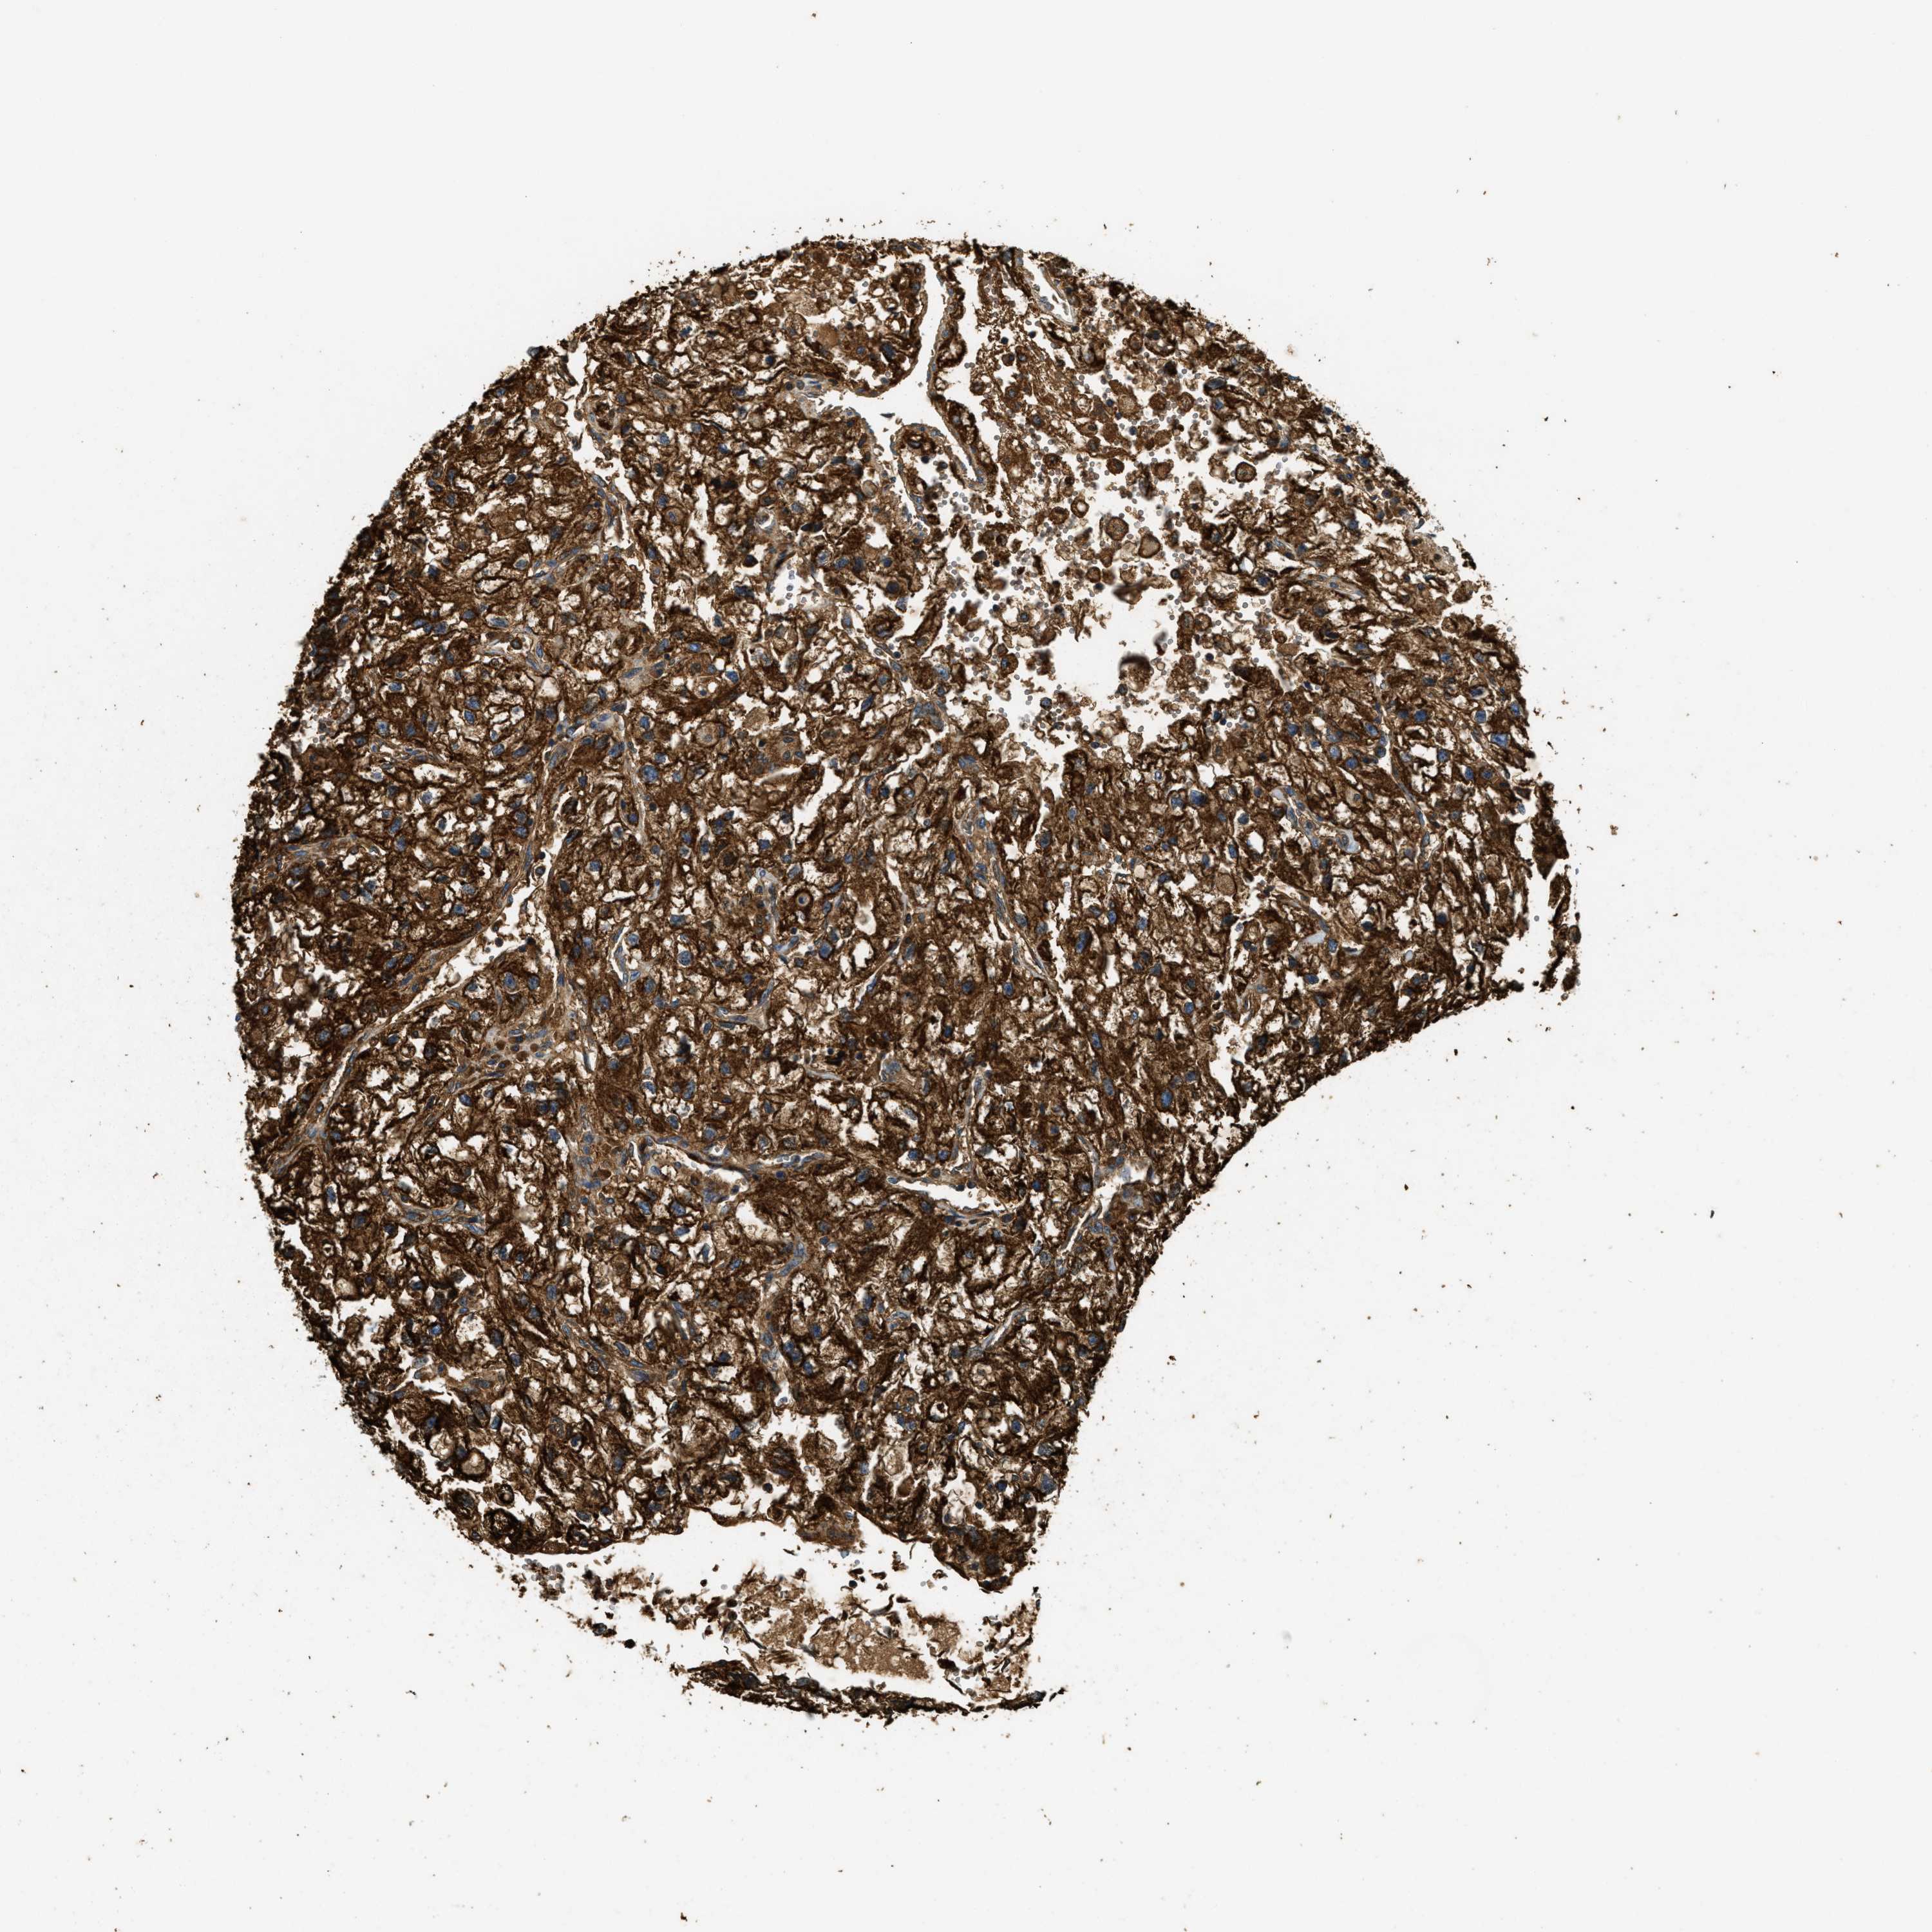

KIDNEY RENAL CLEAR CELL CARCINOMA (VALIDATION) - Interactive survival scatter ploti

The Survival Scatter plot shows the clinical status (i.e. dead or alive) for all individuals in the patient cohort, based on the same data that underlies the corresponding Kaplan-Meier plots. Patients that are alive at last time for follow-up are shown in blue and patients who have died during the study are shown in red.

The x-axis shows the expression levels (FPKM) of the investigated gene in the tumor tissue at the time of diagnosis. The y-axis shows the follow-up time after diagnosis (years). Both axes are complimented with kernel density curves demonstrating the data density over the axes. The top density plot shows the expression levels (FPKM) distribution among dead (red) and alive patients (blue). The right density plot shows the data density of the survived years of dead patients with high and low expression levels respectively, stratified using the cutoff indicated by the vertical dashed line through the Survival Scatter plot. This cutoff is automatically defined based on the FPKM cutoff that minimizes the p-score. The cutoff can be changed by dragging the vertical line or by entering a cutoff value in the square labeled "Current cut-off".

Under the Survival Scatter plot the p-score landscape (black curve; left axis) is shown together with dead median separation (red curve; right axis). Dead median separation is the difference in median mRNA expression between patients who have died with high and low expression, respectively. It is calculated as follows: median FPKM expression of dead patients with high expression - median FPKM expression of dead patients with low expression. This is intended to aid the user in visually exploring custom cutoffs and the associated p-scores and dead median separation.

Individual patient data is displayed and can be filtered by clicking on one or more of the category buttons on the top of the page. Categories describing expression level and patient information include: high, low, alive, dead, female, male and tumor stages. The scale of the x-axis can be toggled between linear and log-scale by clicking on the "x log" button. Mouse-over function shows TCGA ID, patient information and mRNA expression (FPKM) for each patient.

& Survival analysisi

Kaplan-Meier plots summarize results from analysis of correlation between mRNA expression level and patient survival. Patients were divided based on level of expression into one of the two groups "low" (under cut off) or "high" (over cut off). X-axis shows time for survival (years) and y-axis shows the probability of survival, where 1.0 corresponds to 100 percent.

HLCS is not prognostic in Kidney Renal Clear Cell Carcinoma (validation)

TCGA RNA samplesi

RNA-seq data is reported as average FPKM (number Fragments Per Kilobase of exon per Million reads), generated by the The Cancer Genome Atlas (TCGA) .

Normal distribution across the dataset is visualized with box plots, shown as median and 25th and 75th percentiles. Points are displayed as outliers if they are above or below 1.5 times the interquartile range. FPKM values of the individual samples are presented next to the box plot.

Average pTPM 8.3

Number of samples 100